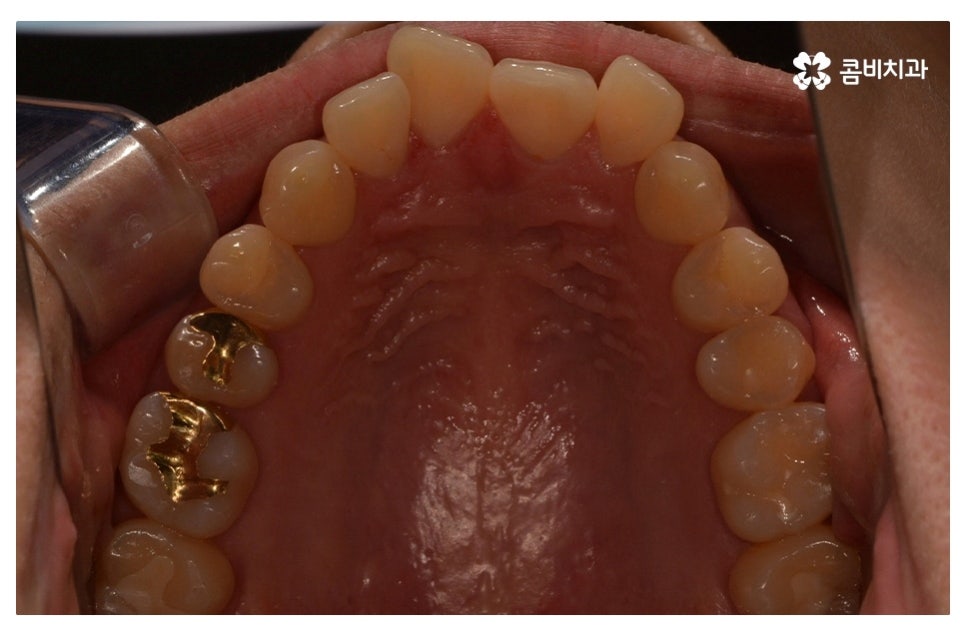

이번 포스팅에서 보인 덧니교정 사례의 경우 기능이 적은 작은 어금니를

발치하여 교정이 진행되었으며 발치를 진행하는 경우

작은 어금니를 발치하는데 충치 등으로 인해 손상이 큰 치아를

발치하는 경우가 일반적이라고 할 수 있어요.

요즘은 교정 장치의 선택에 있어서 다양한 선택이 가능하지만

보편적으로는 본 포스팅의 사례처럼 클리피씨 교정이 많이 선호되고 있어요.

클리피씨 교정은 일반적인 교정보다 치료 기간을 단축시킬 수 있고

통증이 비교적 적으며 세라믹 재질로 심미적이라는 장점이 있어요.